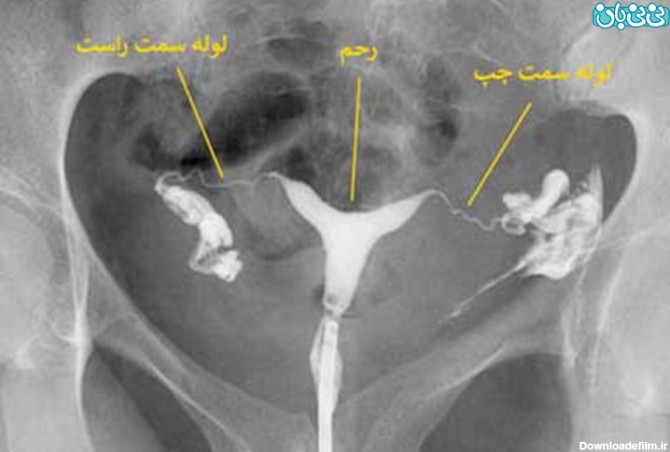

عکس رنگی رحم یا هیستروسالپنگوگرافی یکی از روش های تشخیصی شیوه ی تصویربرداری با اشعه ایکس است که معمولاً برای بررسی آناتومی رحم و لوله ها انجام میشود. عکس رحم

عکس رنگی رحم یا هیستروسالپنگوگرافی روشی جهت تصویربرداری با اشعه ایکس از رحم و لوله های آن است که با تزریق ماده حاجب به آن، در تصاویر رادیولوژی رحم را رویت پذیر کرده و بررسی ناهنجاریهای آن را توسط رادیولوژیست ممکن میسازد.